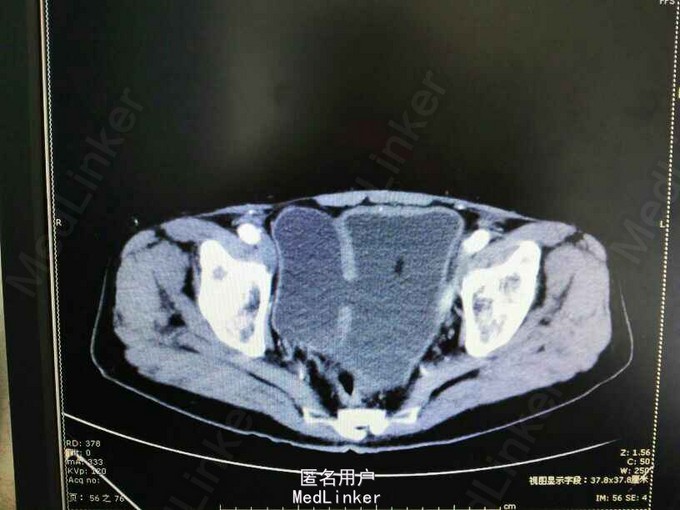

膀胱憩室一例

前列腺增生 膀胱憩室 尿路感染

80岁,男性,因“排尿困难10年,加重伴小便不能自解5小时”入院。既往无高血压、糖尿病等病史。

1.前列腺增生症 尿潴留 膀胱憩室;2.复杂性尿路感染